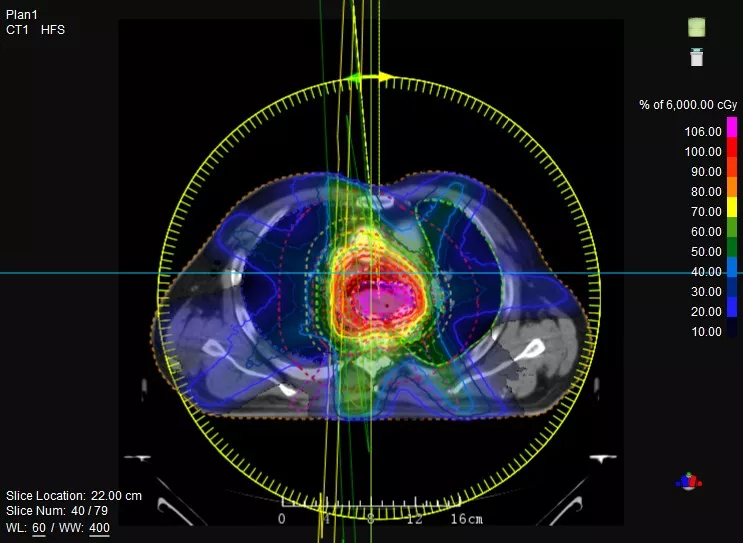

鼻咽癌患者,進(jìn)行旋轉(zhuǎn)容積調(diào)強(qiáng)治療(uARC)